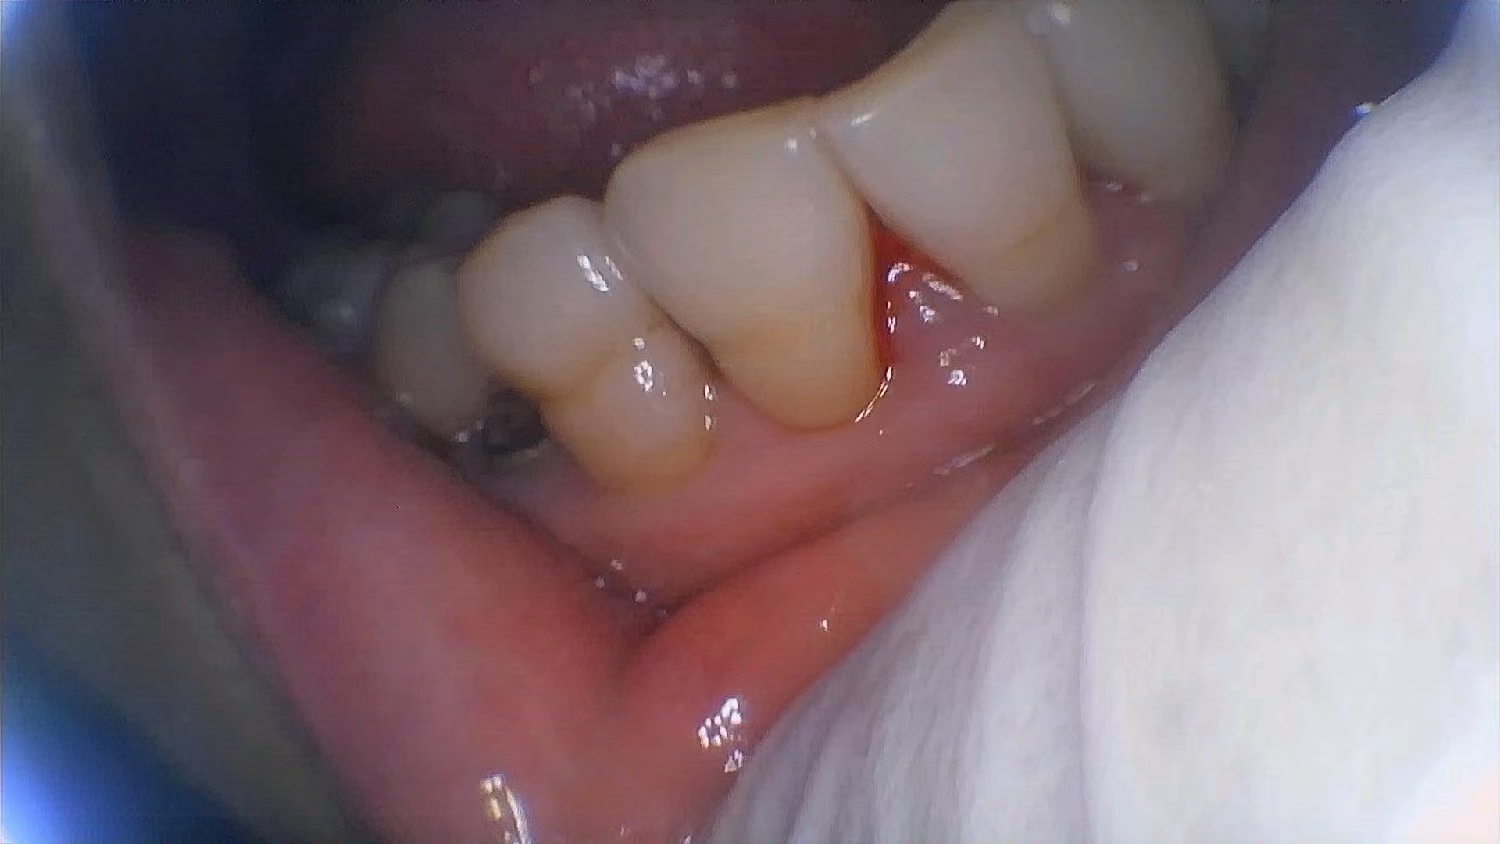

Long-term use of the above two wrong brushing habits will lead to incomplete brushing, tartar hidden in the perfunctory periodontal ligament, and then periodontitis, which requires timely treatment. According to statistics, 70% of adults around the world have gum disease.